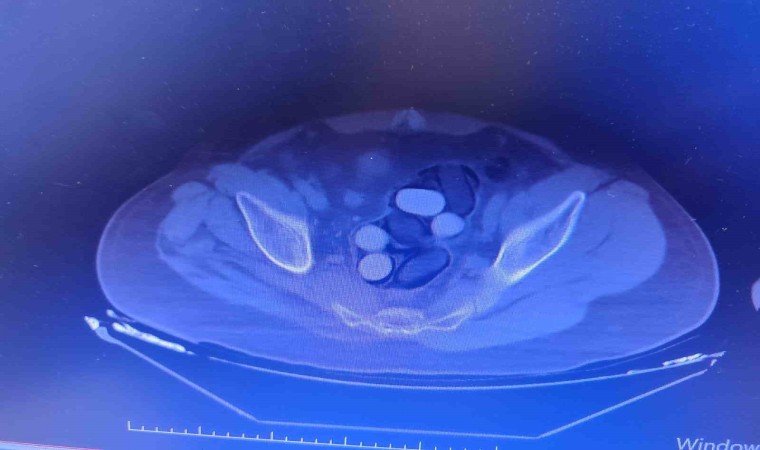

Kırşehir İl Emniyet Müdürlüğü Narkotik Suçlarla Mücadele Şube Müdürlüğü ekipleri tarafından yapılan çalışmalarda yabancı uyruklu Y.S. ve H.S.’nin doğu illerinden ülkeye kaçak yollarla girdikleri ve batı illerine uyuşturucu madde kuryeliği yaptıkları tespit edildi. Takibe alınan uyuşturucu kuryelerinin seyahat ettiği yolcu otobüsü Kırşehir’de durduruldu. Gözaltına alınan ve hastaneye götürülen şahısların midelerinde kapsül bulunduğu tespit edildi. Şahısların midelerinde zulaladığı 126 kapsül halinde 1 kilo 300 gram ve 44 kapsül halinde 550 gram uyuşturucu madde ele geçirildi.